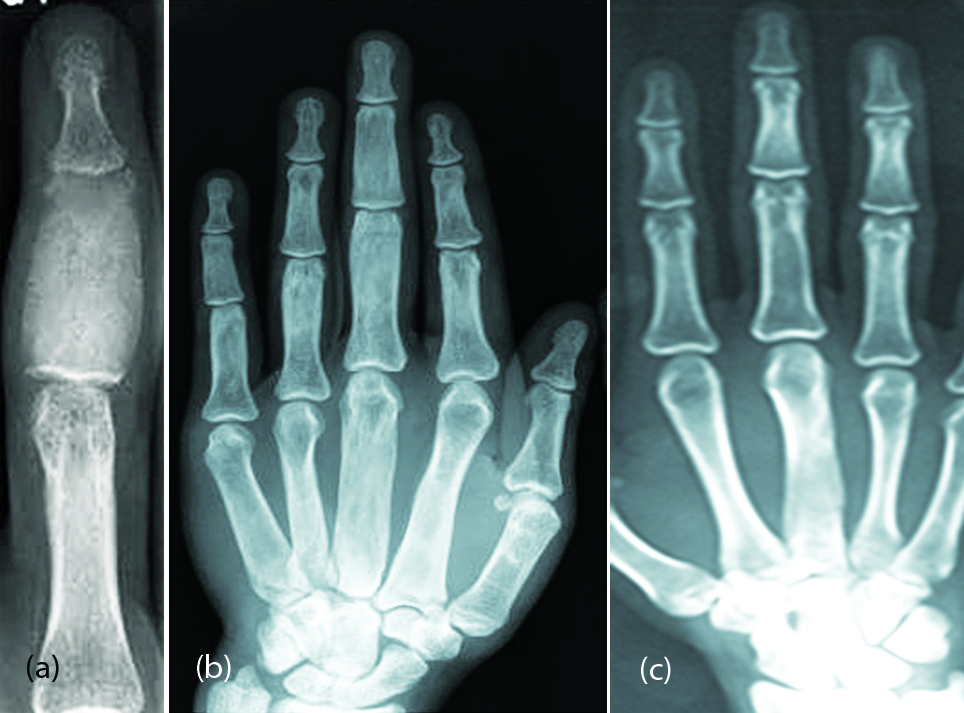

It is a developmental error and generally manifests before puberty. It may be monostotic, polyostotic or part of Albright and mazabraud syndromes [5]. The focal lesion is generally an expanding lytic area with a ground glass appearance (Figure 1a). A well defined border exists with infrequent mineralization of the matrix. Polyostotic fibrous dysplasia involves more than one bone and may be bilateral but not symmetrical (Figure 1b, c). Deformities of the fingers may be noted in but pathological fractures are rare. Similar features are noted in hand bones of Albright’s and mazabraud syndromes.

Figure 1: (a) Monostotic fibrous dysplasia of middle phalanx (Note the ground-glass matrix). (b, c) Polyostotic fibrous dysplasia (Note the ground glass appearance of the bones of the right 3rd finger and 3rd metacarpal of left hand).